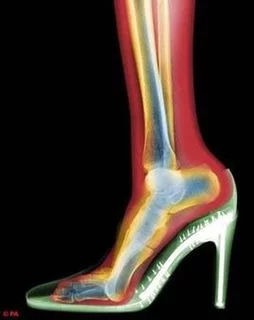

波长介机香永于紫外线和γ射线间的电磁辐射。由德国物理学家W.K.伦琴于1895年发现,故又称伦琴射线。是由x光机产生的高能电磁波。波长比γ射线长,射程略近,穿透力不及γ射线。有危险,应屏蔽(几毫米铅板)。